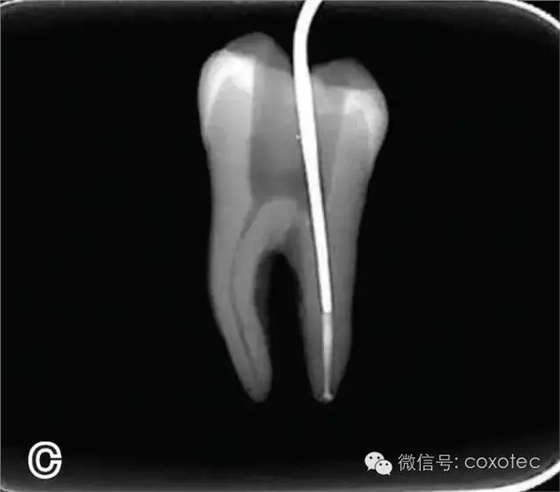

圖2 選擇垂直加壓器,A.試垂直加壓器 B.垂直加壓器在根內的位置 選擇非標準牙膠尖(如0.04、0.06 錐度牙膠尖)作為主尖,型號一般與根管預備最大號的器械型號一致,能到達距根尖0.5~1 mm 處,主尖尖段與根管壁緊密接觸。拍試尖X 線片進行確認(圖3)。

圖3 試尖,A.試主尖 B.拍試尖X片